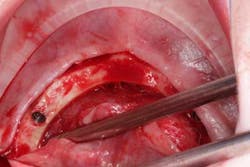

Surgery commenced. Implants on the lower arch were placed first (figures 7 and 8) and then we switched to the maxillary. The teeth were removed (figures 9 and 10) and the ridge was evened out (figures 11-13). The implants were aligned with the denture (figure 14) and then placed accordingly (figures 15-17). Healing caps were put on, and we were ready to start the restorative phase (figures 18-19).

The maxillary arch was indexed first as there was support from the palate to reference position (anterior/posterior) (figure 20). Then the lower was put into position to gain proper vertical dimension and occlusion. It, too, was then indexed; both upper and lower were given to the lab technician to start the conversion process. Next, impression copings were placed (one arch at a time) and secured with paperclips; a full-arch PVS impression was taken and likewise sent to the lab (figures 21-23). Finally, after the conversion process was completed, the bridges were secured in place on the multiunit abutments, torqued to 15nCm, and covered. Bite was adjusted and follow-up care was arranged (figures 24-26).